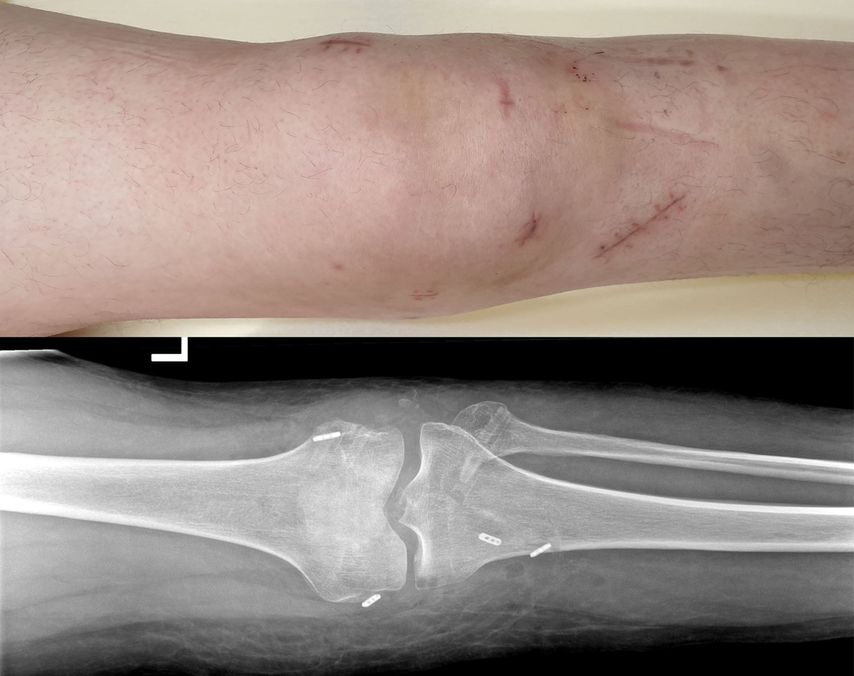

In der Regel wird bei multiligamentären Kniegelenksverletzungen zweizeitig vorgegangen. Hierbei werden primär, innerhalb von 2 Wochen, der mediale und der laterale Bandkomplex (periphere Pfeiler) und sekundär nach ca. 6–8 Wochen das VKB und HKB mittels Auto- oder Allograft rekonstruiert (Abb.3, 4).12

Nach primärer Reposition sollte die Retention im Gipsverband oder mittels eines Fixateur externe erzielt werden. Besteht zusätzlich eine Nerven- oder eine nicht zwingend zu behandelnde Gefäßläsion, wird im Allgemeinen eher zu einem Fixateur externe geraten, um den verletzten Strukturen mehr Ruhe zu geben.

Aufgrund neuer chirurgischer Techniken und Implantate erfährt die Sehnenrefixation eine Renaissance. Durch zusätzliche Augmentation der Refixationen mit einem Fiber-Tape („ligament bracing“) kann die Primärstabilität erhöht werden. Das Fiber-Tape fungiert als eine Art Sicherheitsgurt, bis das native Band wieder ossär integriert ist. Frosch et al.konnten mit einer primären Refixation und zusätzlichem „ligament bracing“ ähnlich gute Ergebnisse wie bei einer Rekonstruktion erzielen.15